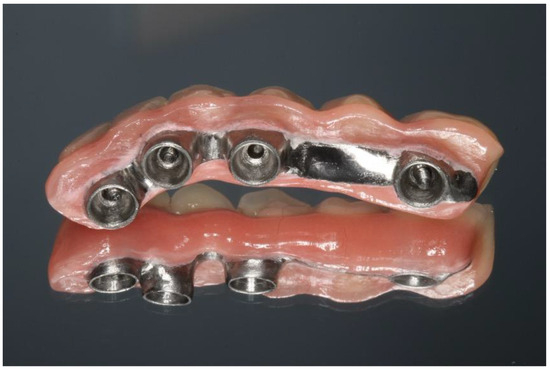

2.1. Case 1

2.2. Case 2